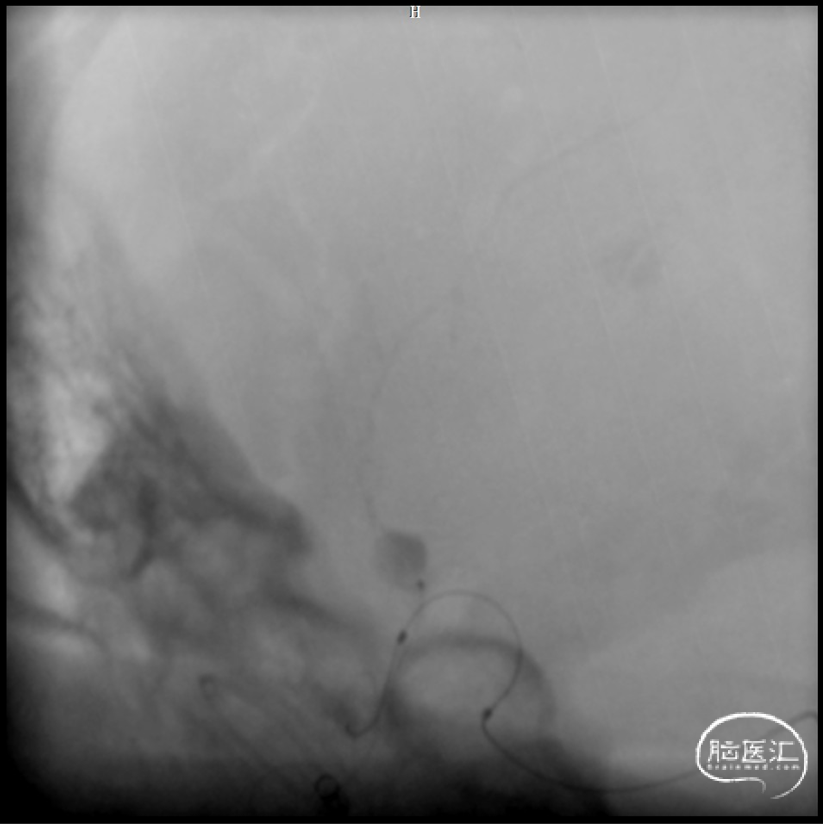

微导管超选

球囊保护下微导管造影证实假性动脉瘤

球囊保护下25%gb栓塞